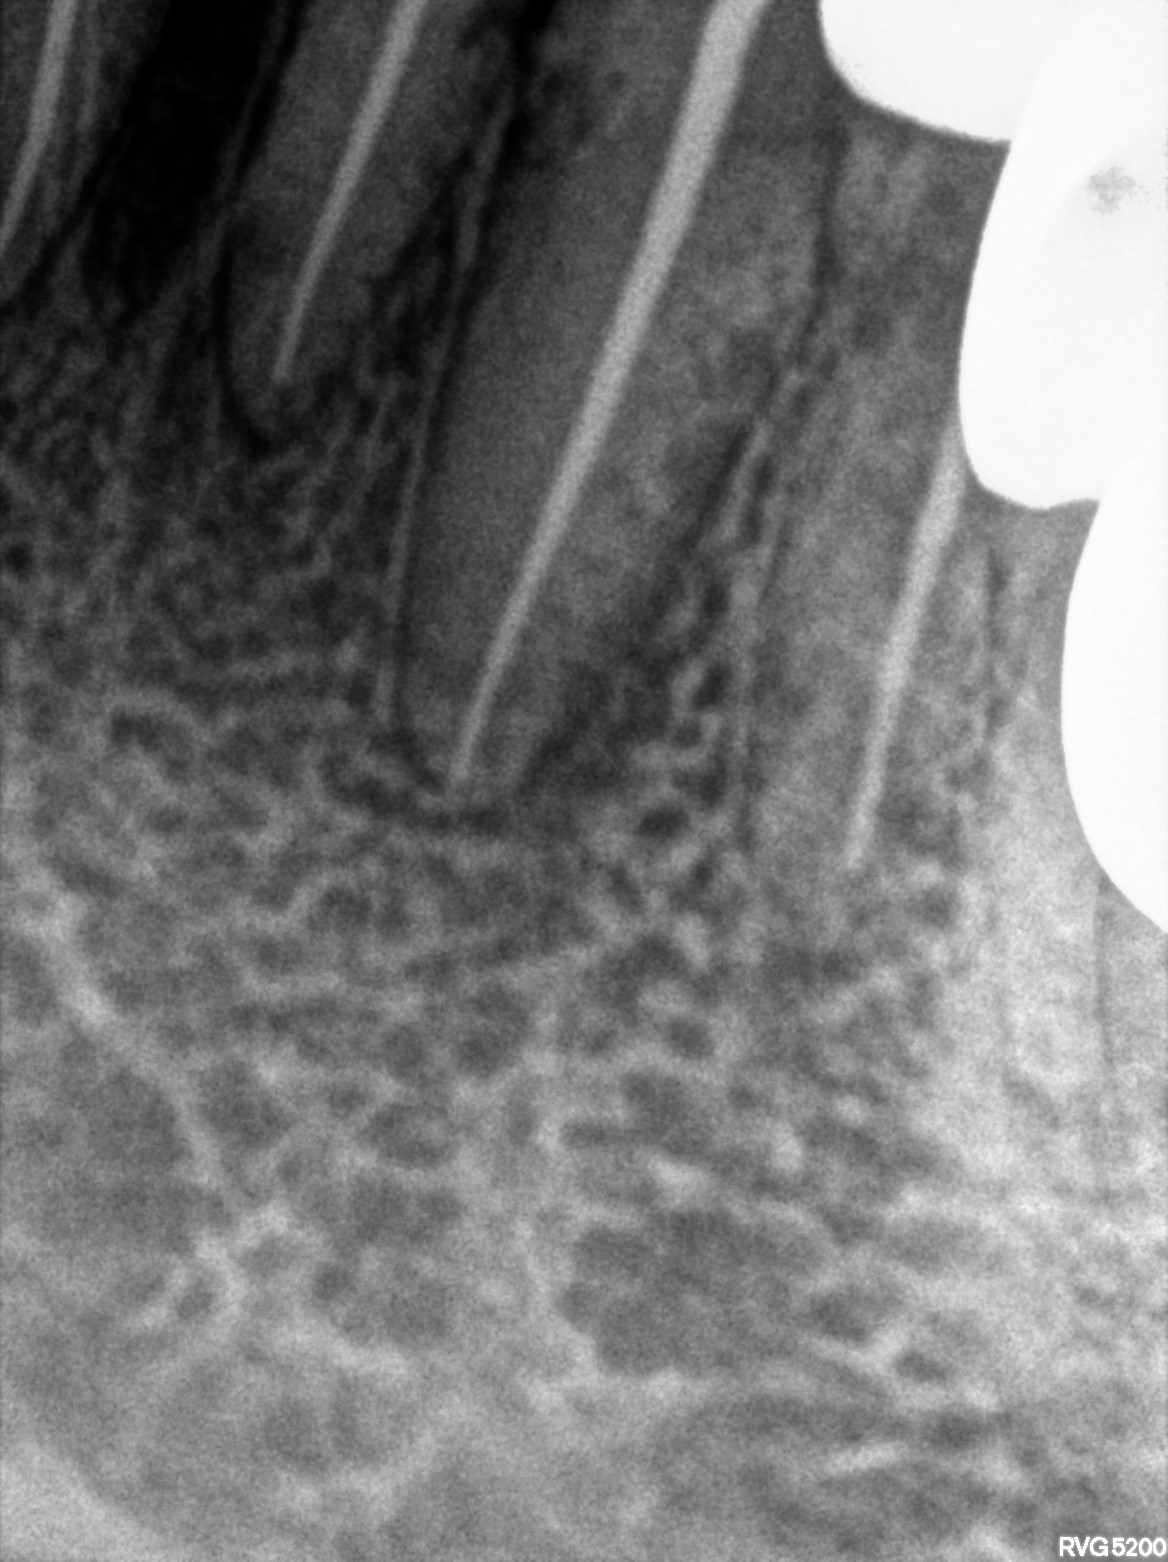

Dental Radiographs FHIR: DocumentReference · LOINC 24641-7

d (14).jpg

24641-7